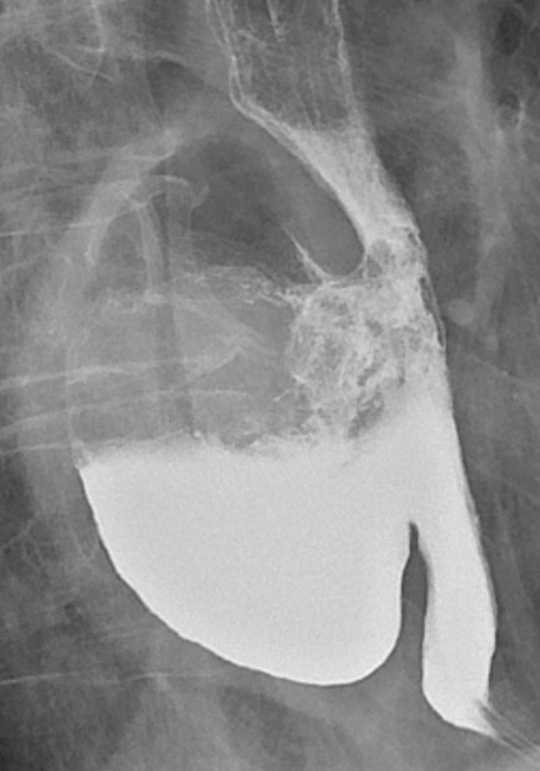

Post-operative time in hospital was a median of 16.5 days (range 5 – 45 days). For the eight patients without serious complications, it was ten days (5 – 16 days). The median longest diameter of an extirpated diverticulum (Fig. 1) was 5 cm (range 3.5 – 9 cm). The neck of the diverticulum at the oesophagus was a median of 3 cm (range 1.5 – 5 cm).

Figure 1  Large, partly contrast-filled epiphrenic oesophageal diverticulum facing towards the right in the mediastinum